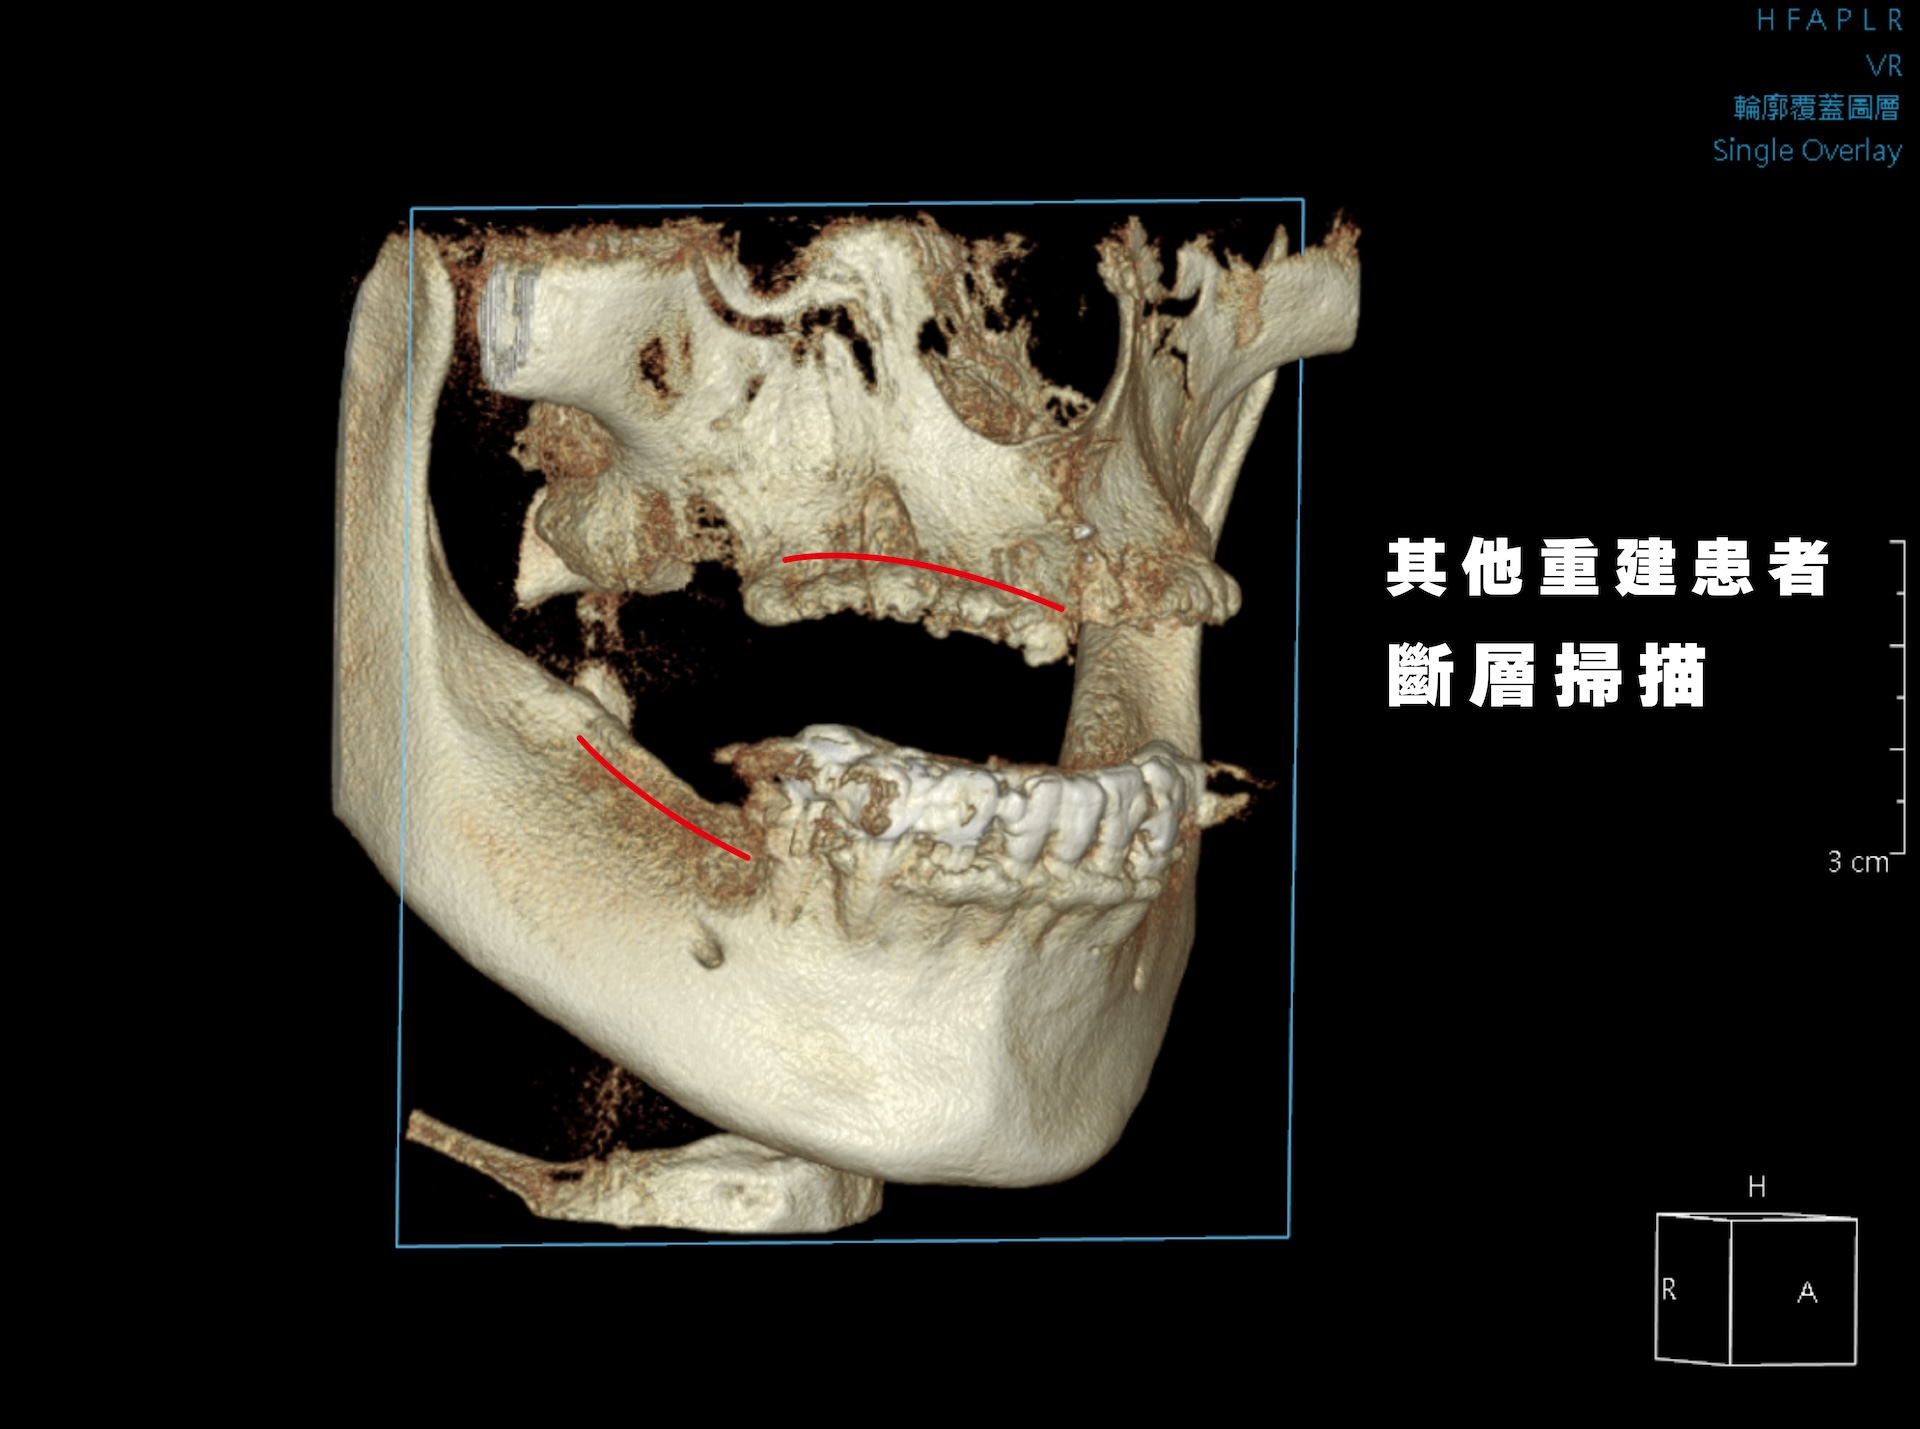

蒔美全口重建中心主任、口腔顎面外科專科賴泓璋醫師透過全頭顱電腦斷層與數位口掃精準評估齒槽骨與牙齦狀態,再深入了解他對咬合、外觀與生活品質的需求。

Dr. Hung-Chang Lai, head of the Full-Mouth Reconstruction Center, used craniofacial CBCT scan and a 3Shape intraoral scanner to assess his condition, then listened closely to his concerns.

若採傳統重建,療程需多年且多次補骨,恐影響教學。最終,團隊為他規劃諾保科 All-on-4,全程一天即可完成植體與假牙銜接,幾乎無縫回歸日常。

Traditional treatment would have meant years of bone grafts and delays. Instead, the team turned to Nobel Biocare’s All-on-4, restoring his teeth in a single day and allowing him to return to life without interruption.